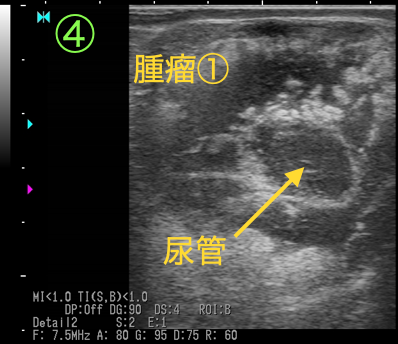

断面①

腎盂が拡張しています。右に示す他の牛と比較することでよくわかります。

以上の画像と触診から、腫瘤①が尿管を巻き込むように形成されており、巻き込まれた尿管は著しく狭窄し(③④)、腎盂および腫瘤より腎臓側の尿管は鬱滞した尿により著しく拡張している(①②)ことがわかりました。